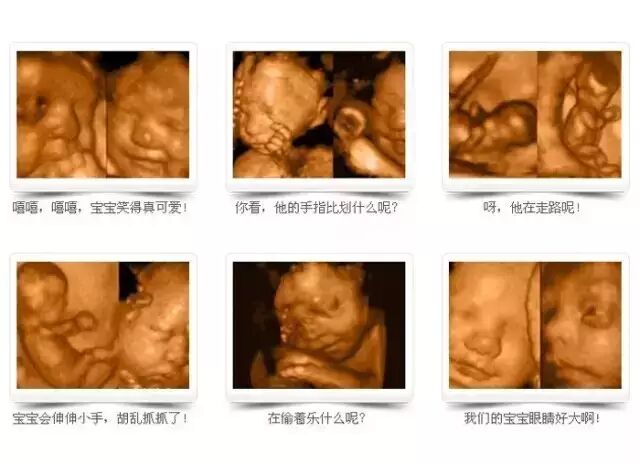

可视

5D四维,能自动为胎儿进行宫内拍“写真”和动态录像,为准妈妈增添了不少情趣。她们不再是仅仅感觉宝宝运动,而且可以亲眼目睹肚子里宝宝的乖巧容貌和可爱动作。